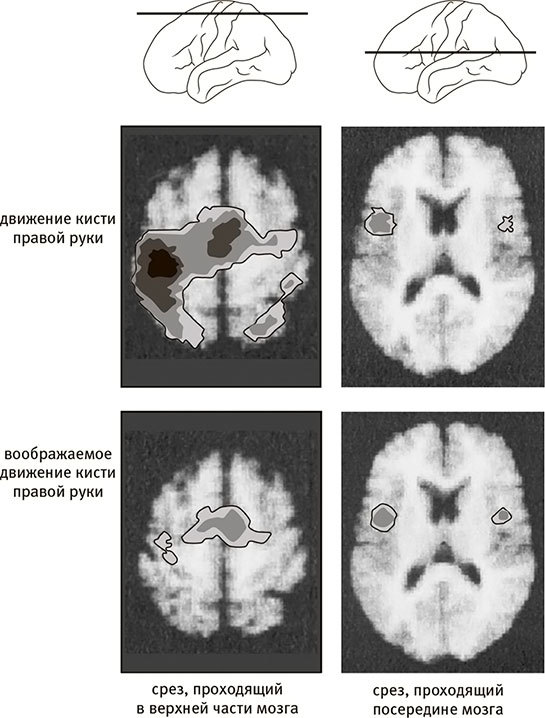

Рис. п.7. Результаты сканирования мозга во время реальных и воображаемых движений

На схемах вверху показано, как проходят срезы мозга (в верхней части и посередине), на которых видна мозговая активность. На верхних срезах показана активность, наблюдаемая, когда испытуемый двигает правой рукой, а на нижних – активность, наблюдаемая, когда испытуемый только представляет себе, что двигает правой рукой.